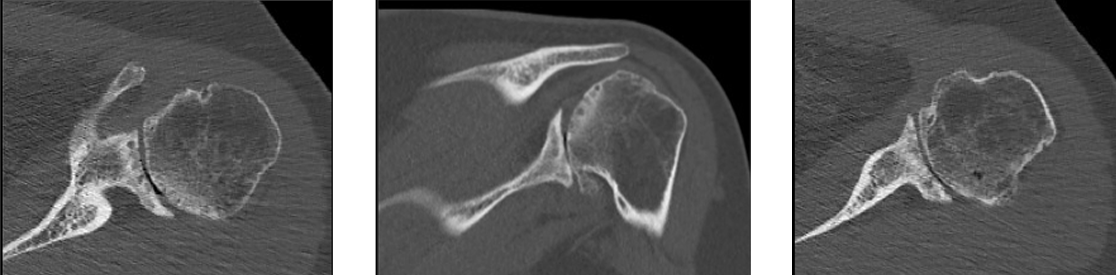

Pre-op

- 43-year-old female patient

- Primary shoulder osteoarthritis

- No cuff tear, no rotator cuff muscle atrophy

- Severe pain, poor function

- Anterior flexion 70°; external rotation 20°